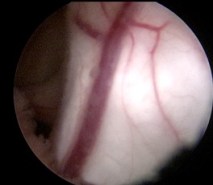

la découverte d’une dissémination tumorale lors de l’endoscopie (ci-dessus) est une mauvaise surprise, qui fait craindre un échec de la stomie s’il existe un feutrage arachnoïdien.